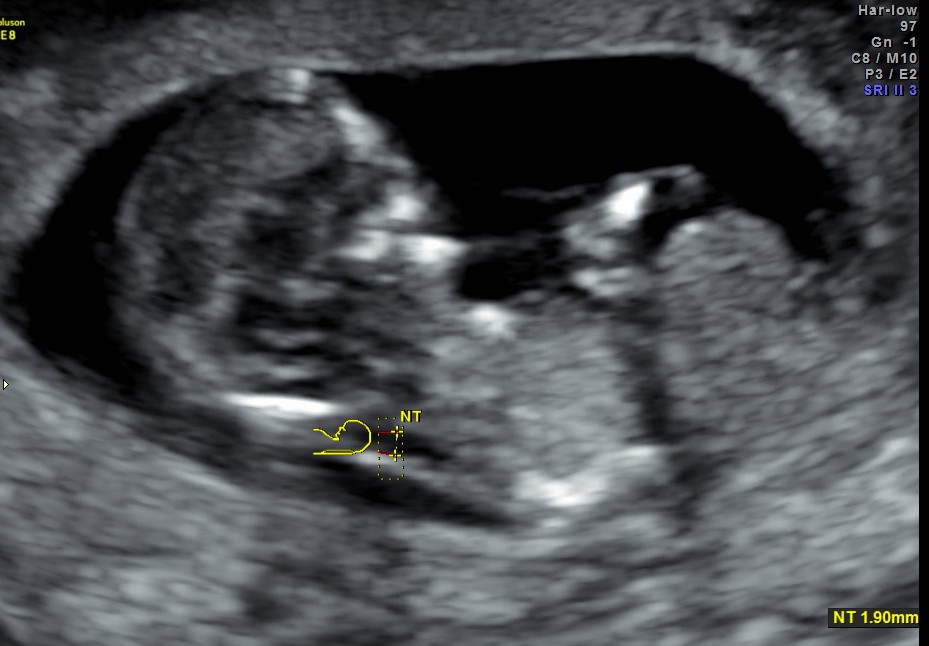

This was a 19 year old primi with history of consanguinity.The scan was done in the first trimester.

- on a first trimester scan ( 10 – 14 weeks)

- if the longitudinal bladder diameter of 7 – 15 mm there is a risk of a chromosomal defects is esimated at ~ 25% 4

- if the bladder diameter is > 15 mm the risk of chromosomal defects is estimated at ~ 10% 4